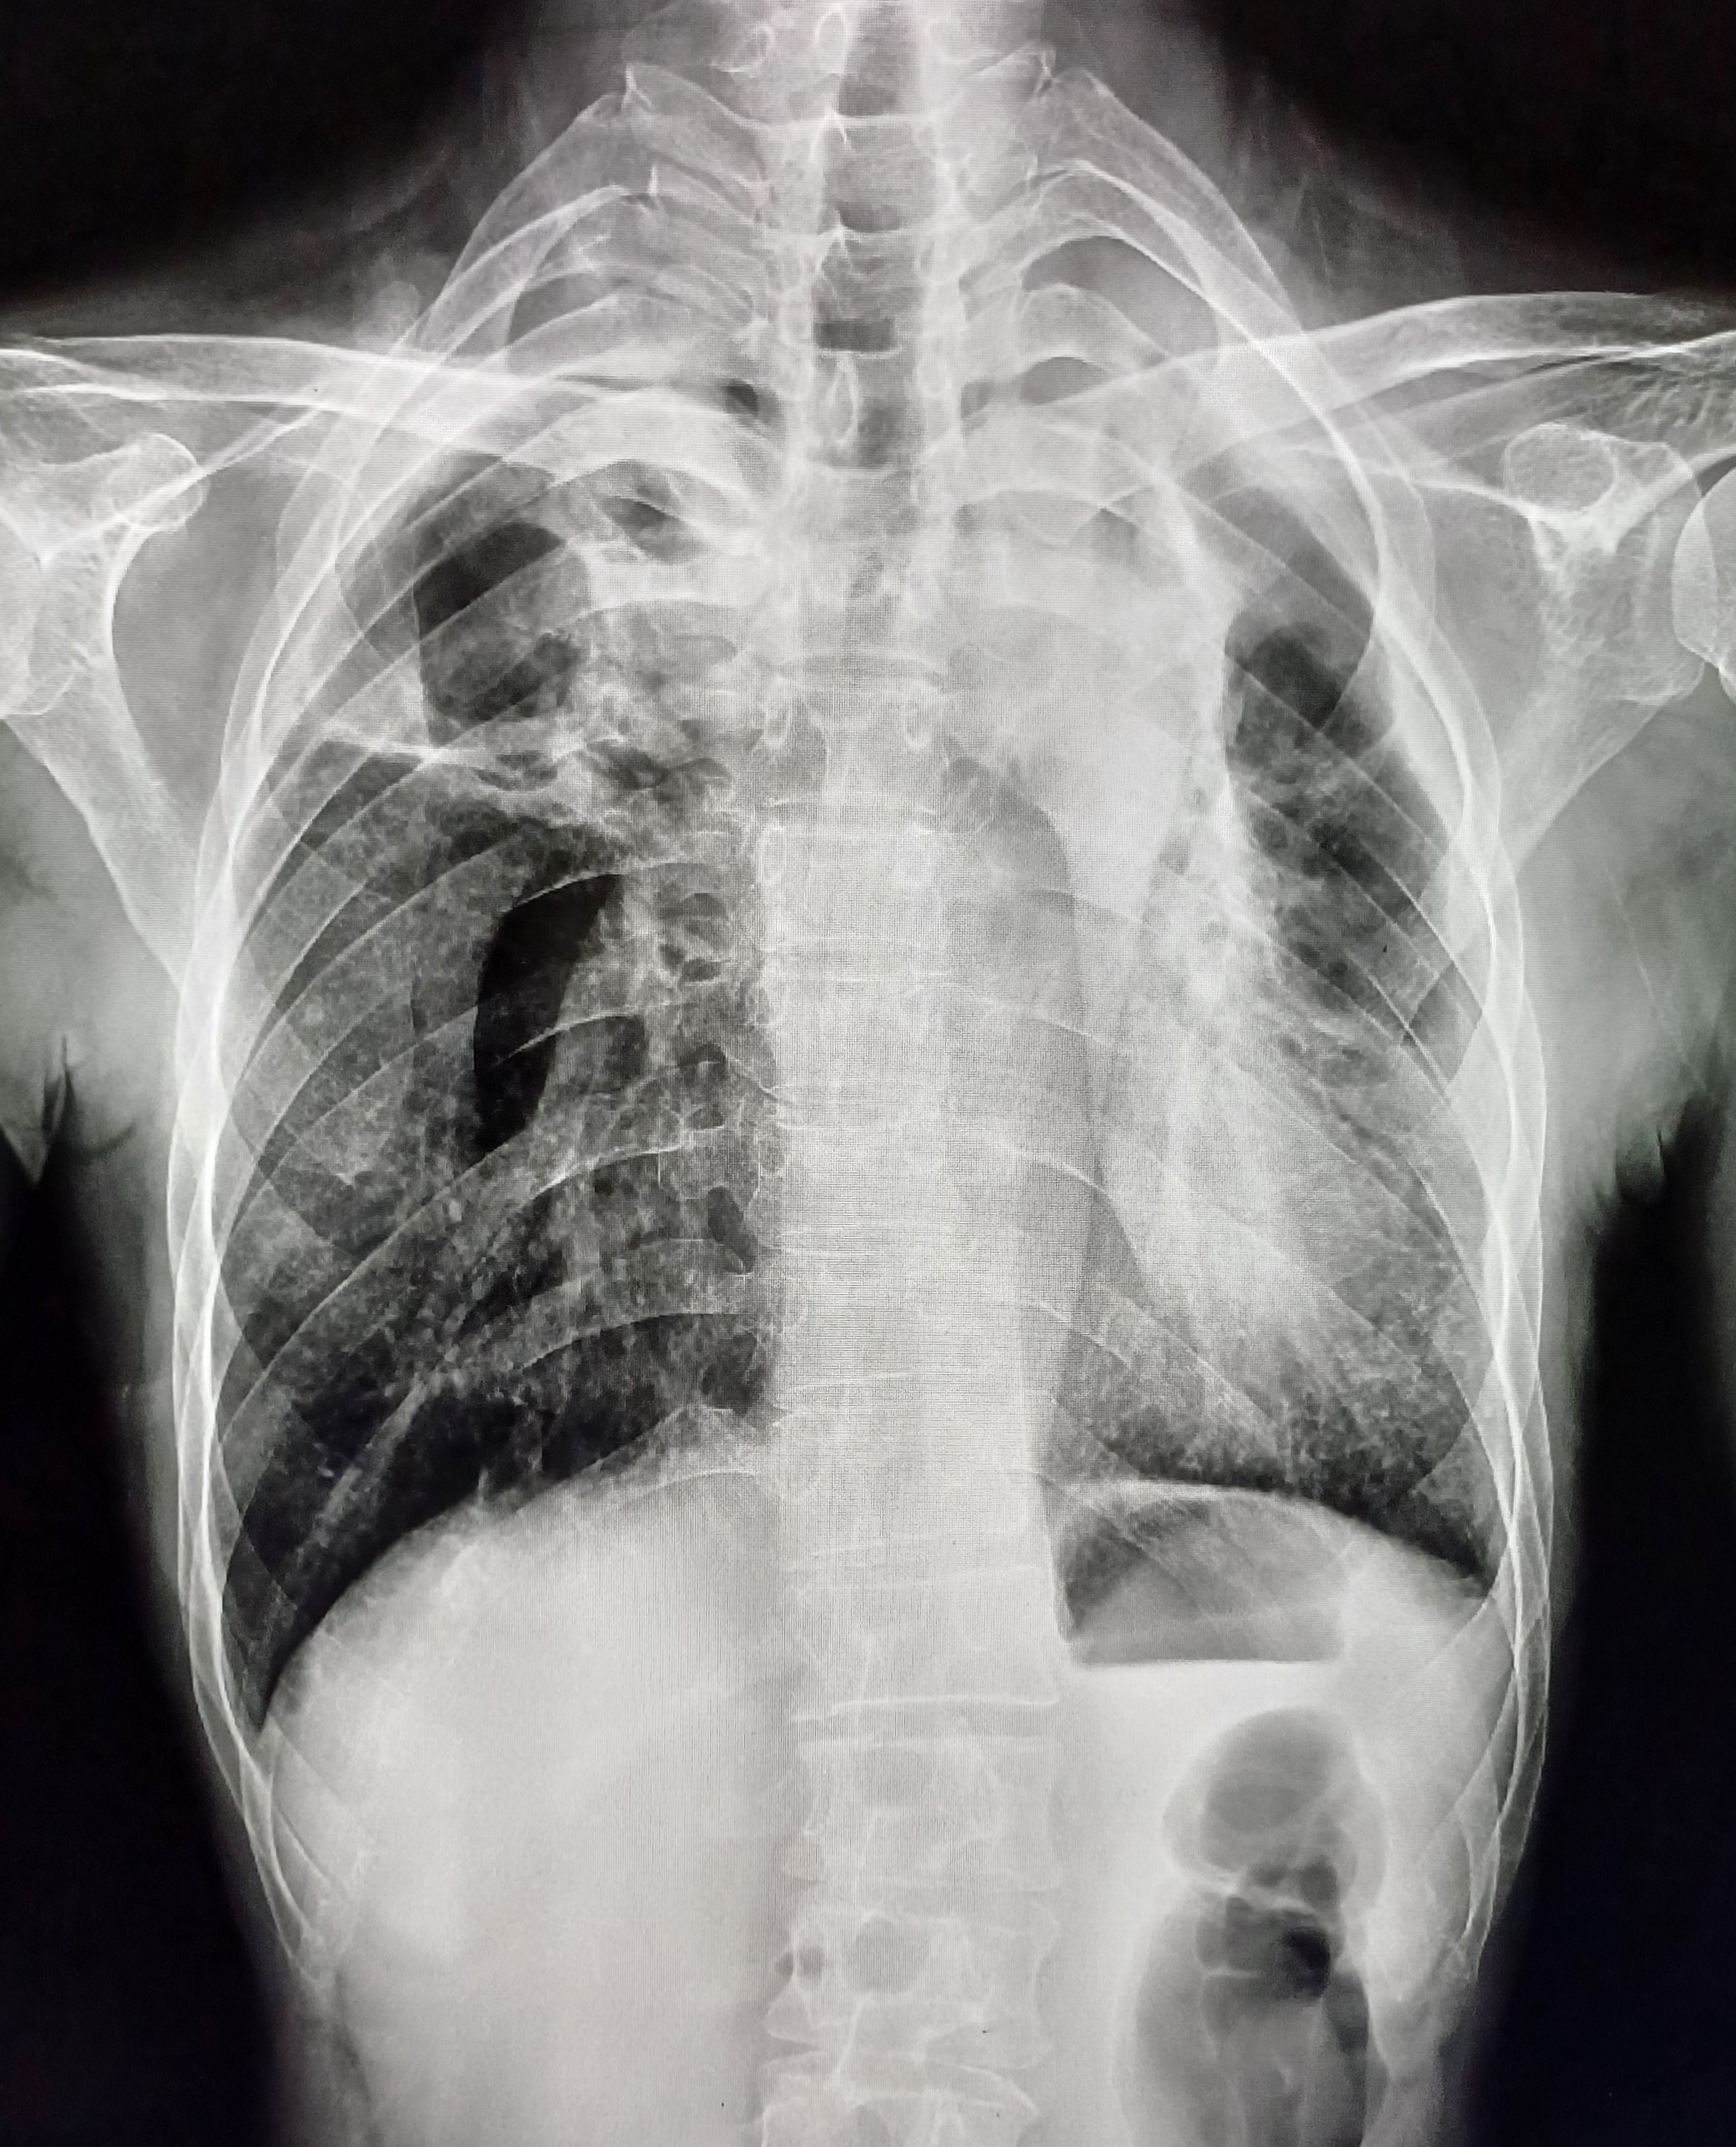

| 4 | IGGMC, Nagpur, Nagpur | P2 | 29-4468 | Moh. Salehuddin | Consent taken on Paper | 68 Yrs. |

Provisional Diag : Miliary TB?

Final Diag : Miliary TB |

TB Case (Confirmed) | Bilateral Infiltrate Query Miliary | Abnormality visible on x-ray |